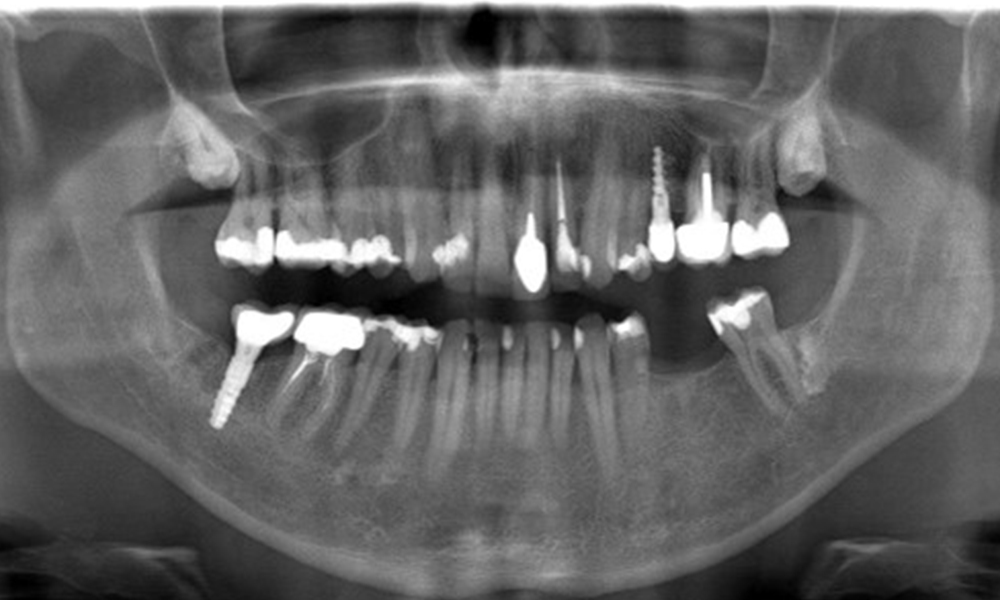

OPG: 29/02/2024

X-ray images (or bitewing X-rays)

X-ray images (or bitewing X-rays) taken on: 18/02/2021